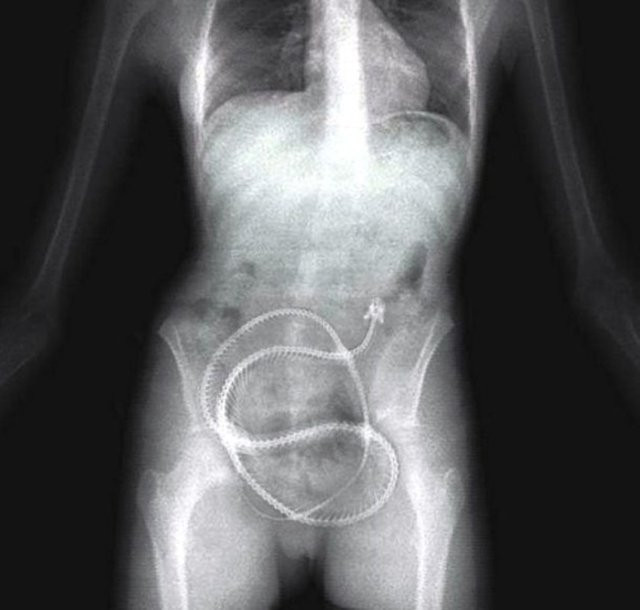

Yılan balığı